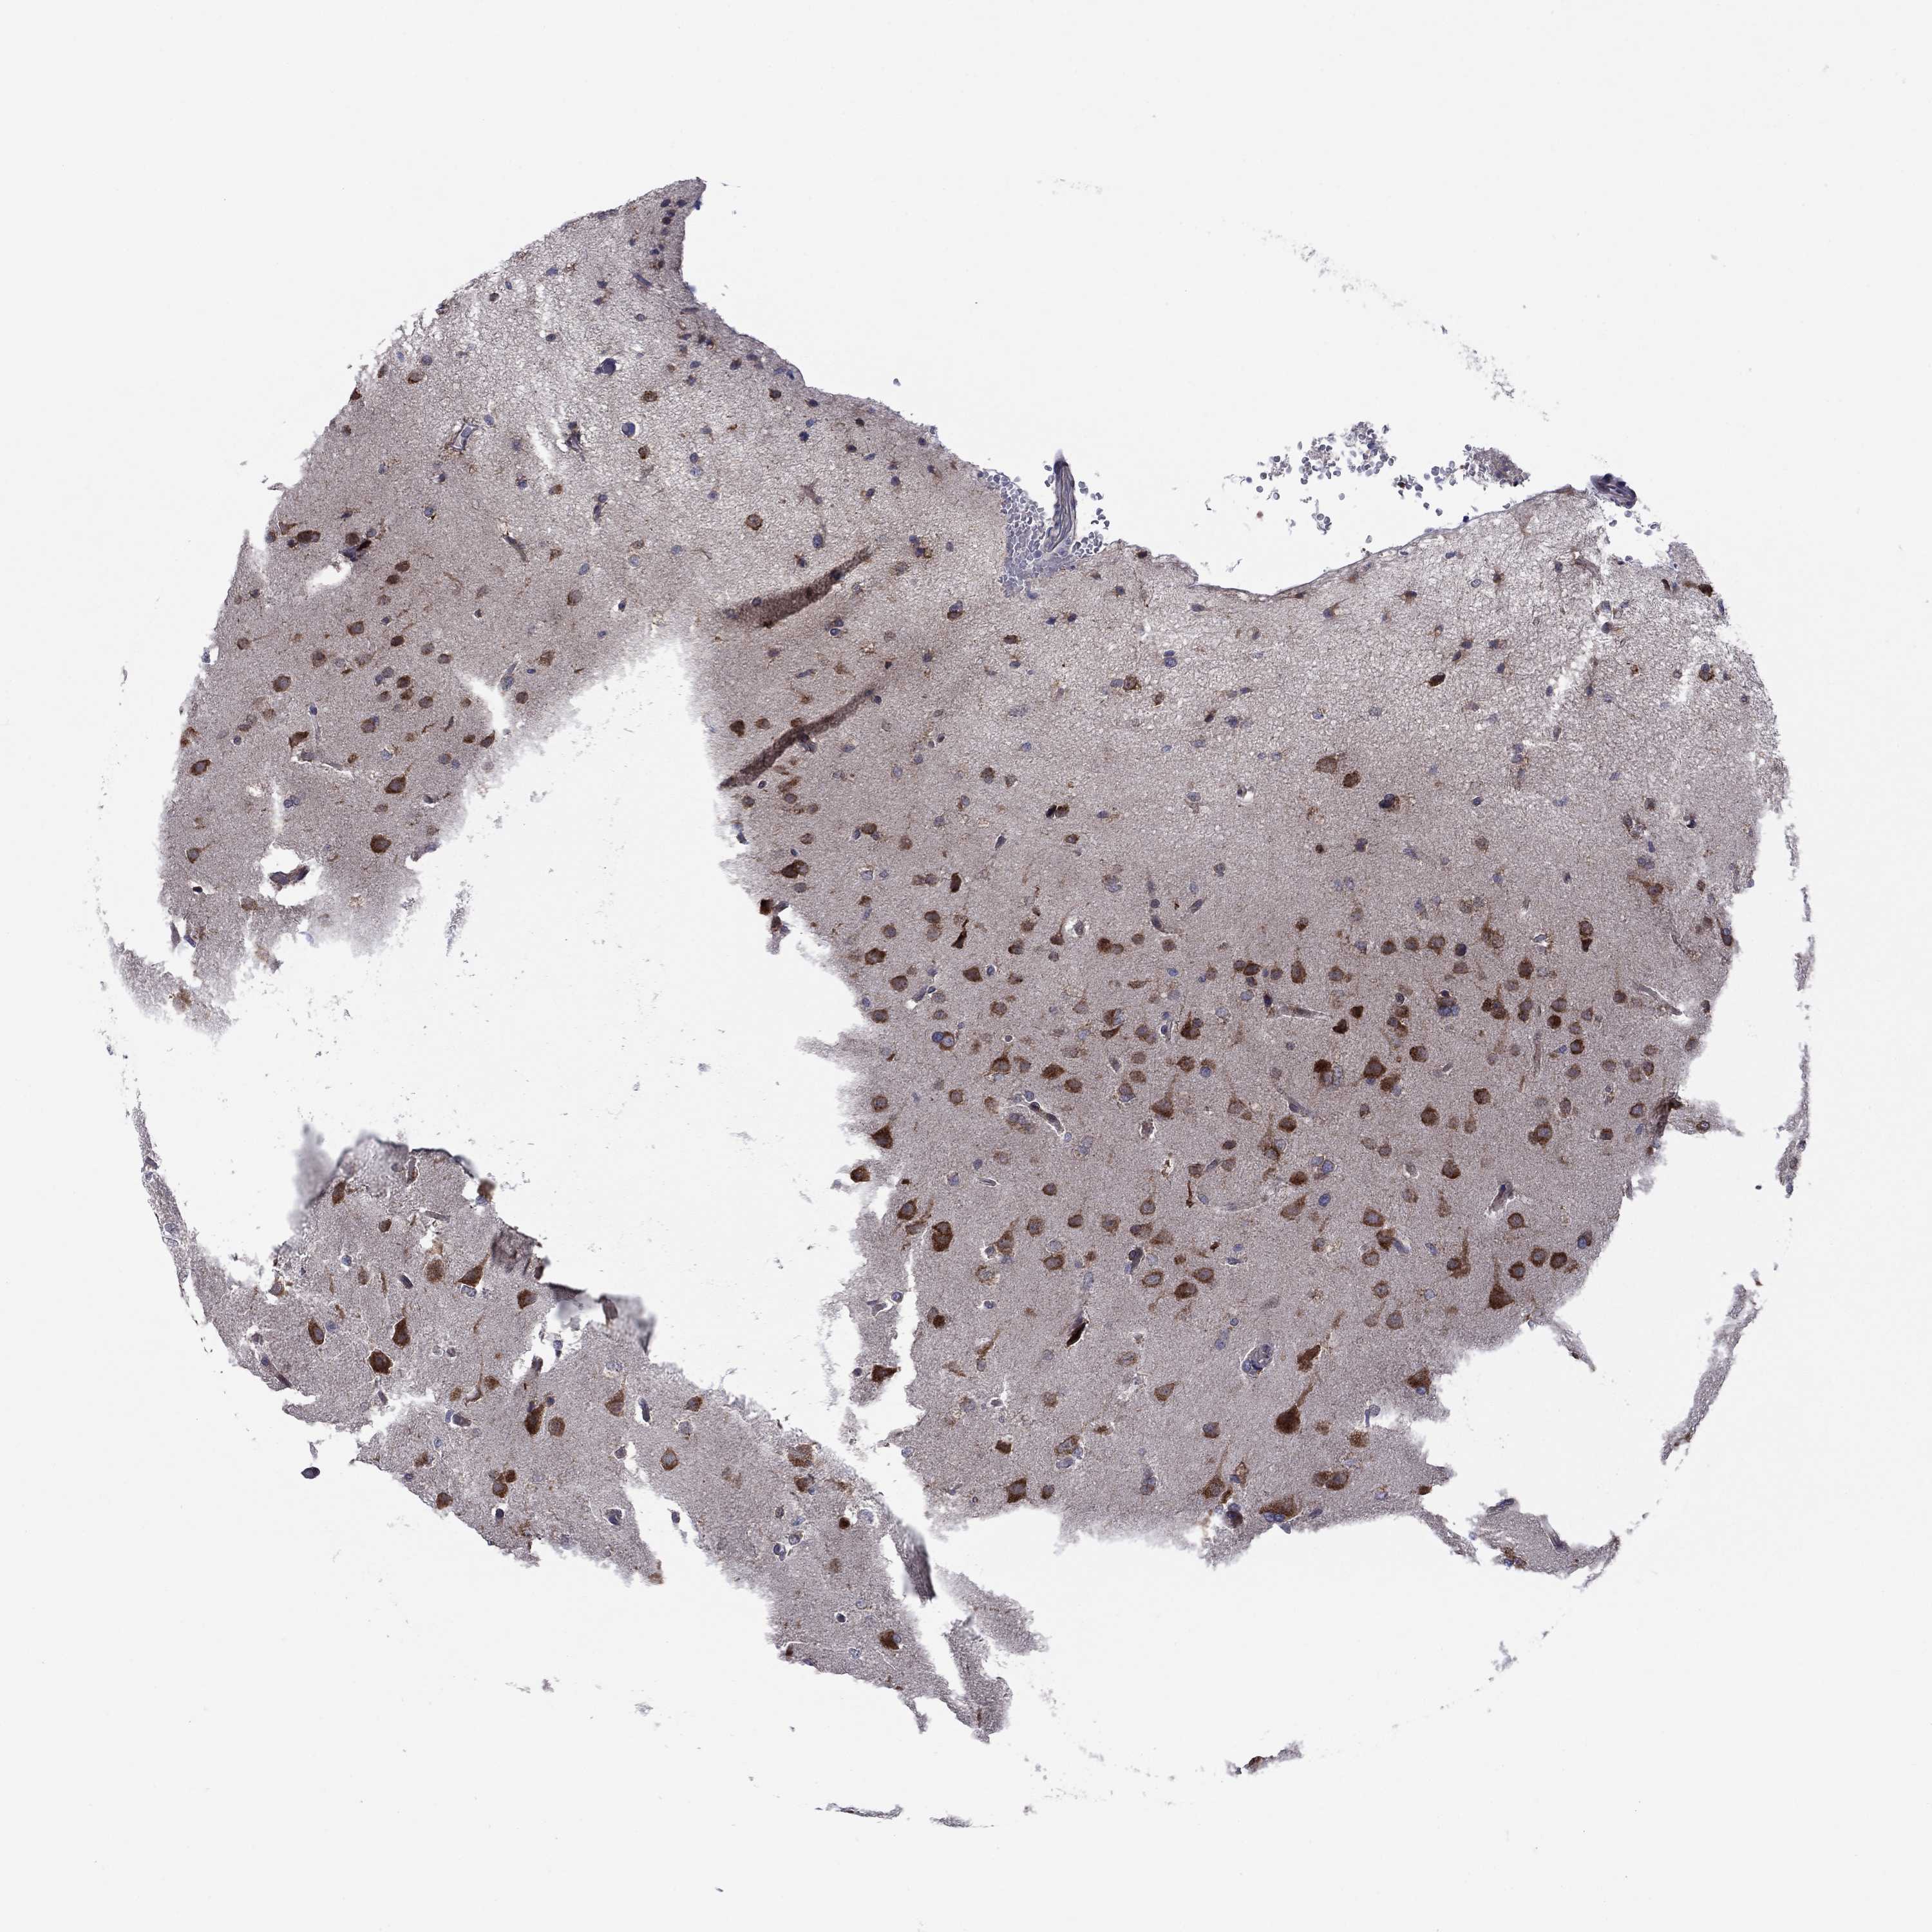

GLIOMA - Protein expressioni

A mouse-over function shows sample information and annotation data. Click on an image to view it in a full screen mode. Samples can be filtered based on level of antibody staining by selecting one or several of the following categories: high, medium, low and not detected. The assay and annotation is described here.

Note that samples used for immunohistochemistry by the Human Protein Atlas do not correspond to samples in the TCGA dataset.

Antibody stainingi

Antibody staining in the annotated cell types in the current human tissue is reported as not detected, low, medium, or high, based on conventional immunohistochemistry profiling in selected tissues. This score is based on the combination of the staining intensity and fraction of stained cells.

Each image is clickable and will lead to virtual microscopy that enables deeper exploration of all samples and also displays staining intensity scores, fraction scores and subcellular localization as well as patient and tissue information for each sample.

Antibody HPA036159

Antibody HPA057384

Staining

High

Medium

Low

Not detected

Intensity

Strong

Moderate

Weak

Negative

Quantity

>75%

75%-25%

<25%

None

Location

Nuclear

Cytoplasmic/membranous

Cytoplasmic/membranous,nuclear

Glioma, malignant, High grade

Glioma, malignant, Low grade

Glioblastoma, NOS

Glioma, malignant, NOS